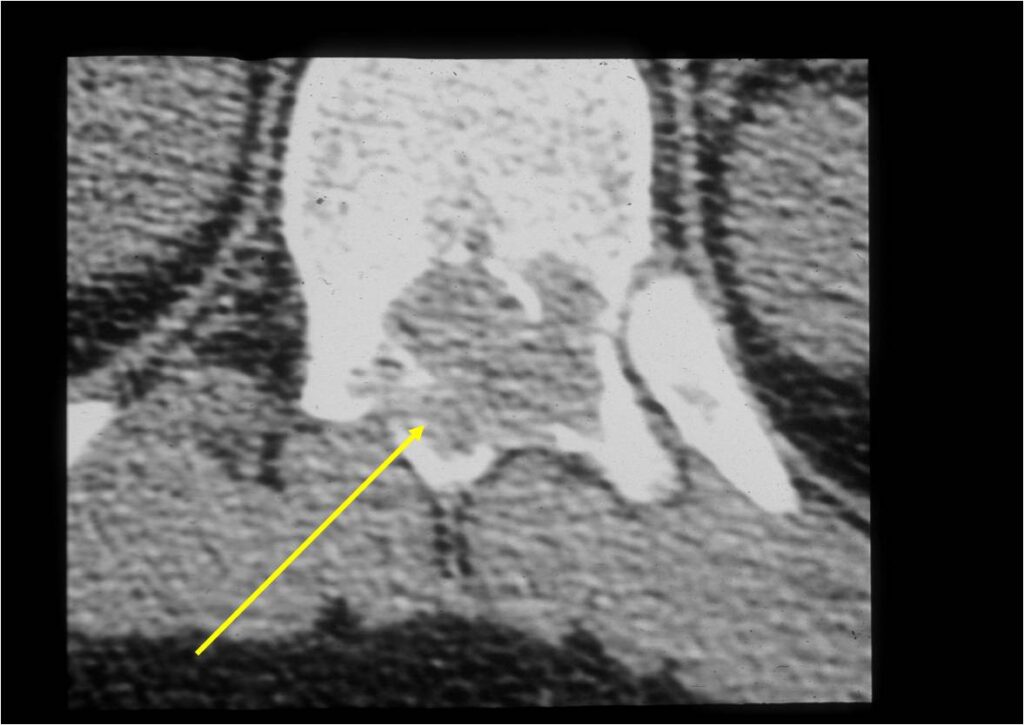

- Spine (40% of cases; usually posterior elements)

CT Scan:

- More useful for detecting mineralization and evaluating extent of bone destruction than plain X-ray

- Also useful in determining extent

- There is often extensive edema around the tumor in the surrounding bone and soft tissues that can lead to a misdiagnosis of a malignant tumor.